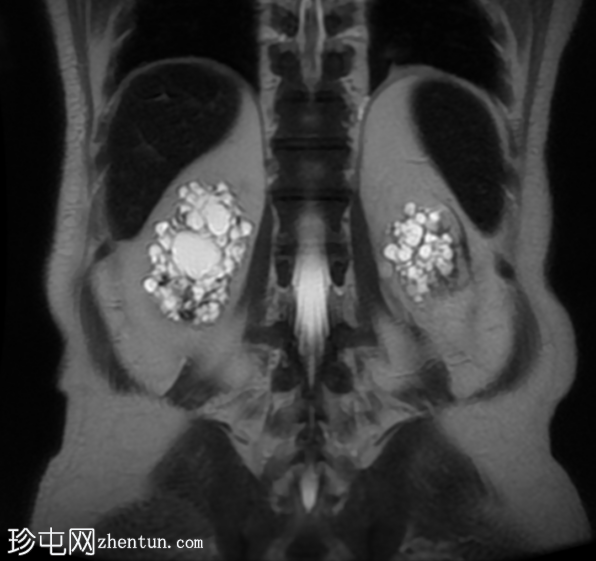

轴位

STIR序列

双侧肾囊性疾病,可见多个肾囊肿,其中许多呈复杂性(出血性)囊肿,T1加权像呈高信号,T2加权像呈低信号。

左侧可见一较大的肾周血肿,与上极出血性囊肿相连,提示出血性囊肿破裂(Wunderlich综合征)。

未见肾脏软组织肿块。

轻度肝脾肿大,受检骨骼T2加权像呈弥漫性低信号,提示肾性骨营养不良。